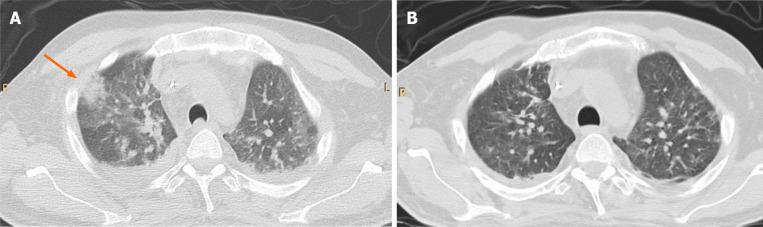

Invasive infections are a major complication before liver transplantation (LT) and in the early phase after surgery. There has been an increasing prevalence of invasive fungal disease (IFD), especially among the sickest patients with decompensated cirrhosis and acute-on-chronic liver failure, who suffer from a profound state of immune dysfunction and receive intensive care management. In such patients, who are listed for LT, development of an IFD often worsens hepatic and extra-hepatic organ dysfunction, requiring a careful evaluation before surgery. In the post-transplant setting, the burden of IFD has been reduced after the clinical advent of antifungal prophylaxis, even if several major issues still remain, such as duration, target population and drug type(s). Nevertheless, the development of IFD in the early phase after surgery significantly impairs graft and patient survival. This review outlines presentation, prophylactic and therapeutic strategies, and outcomes of IFD in LT candidates and recipients, providing specific considerations for clinical practice.